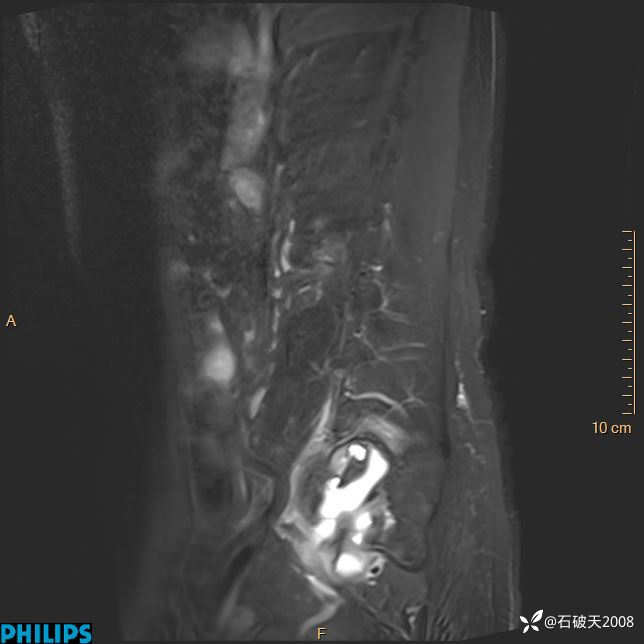

2023年3月份MRI影像

T2矢状位